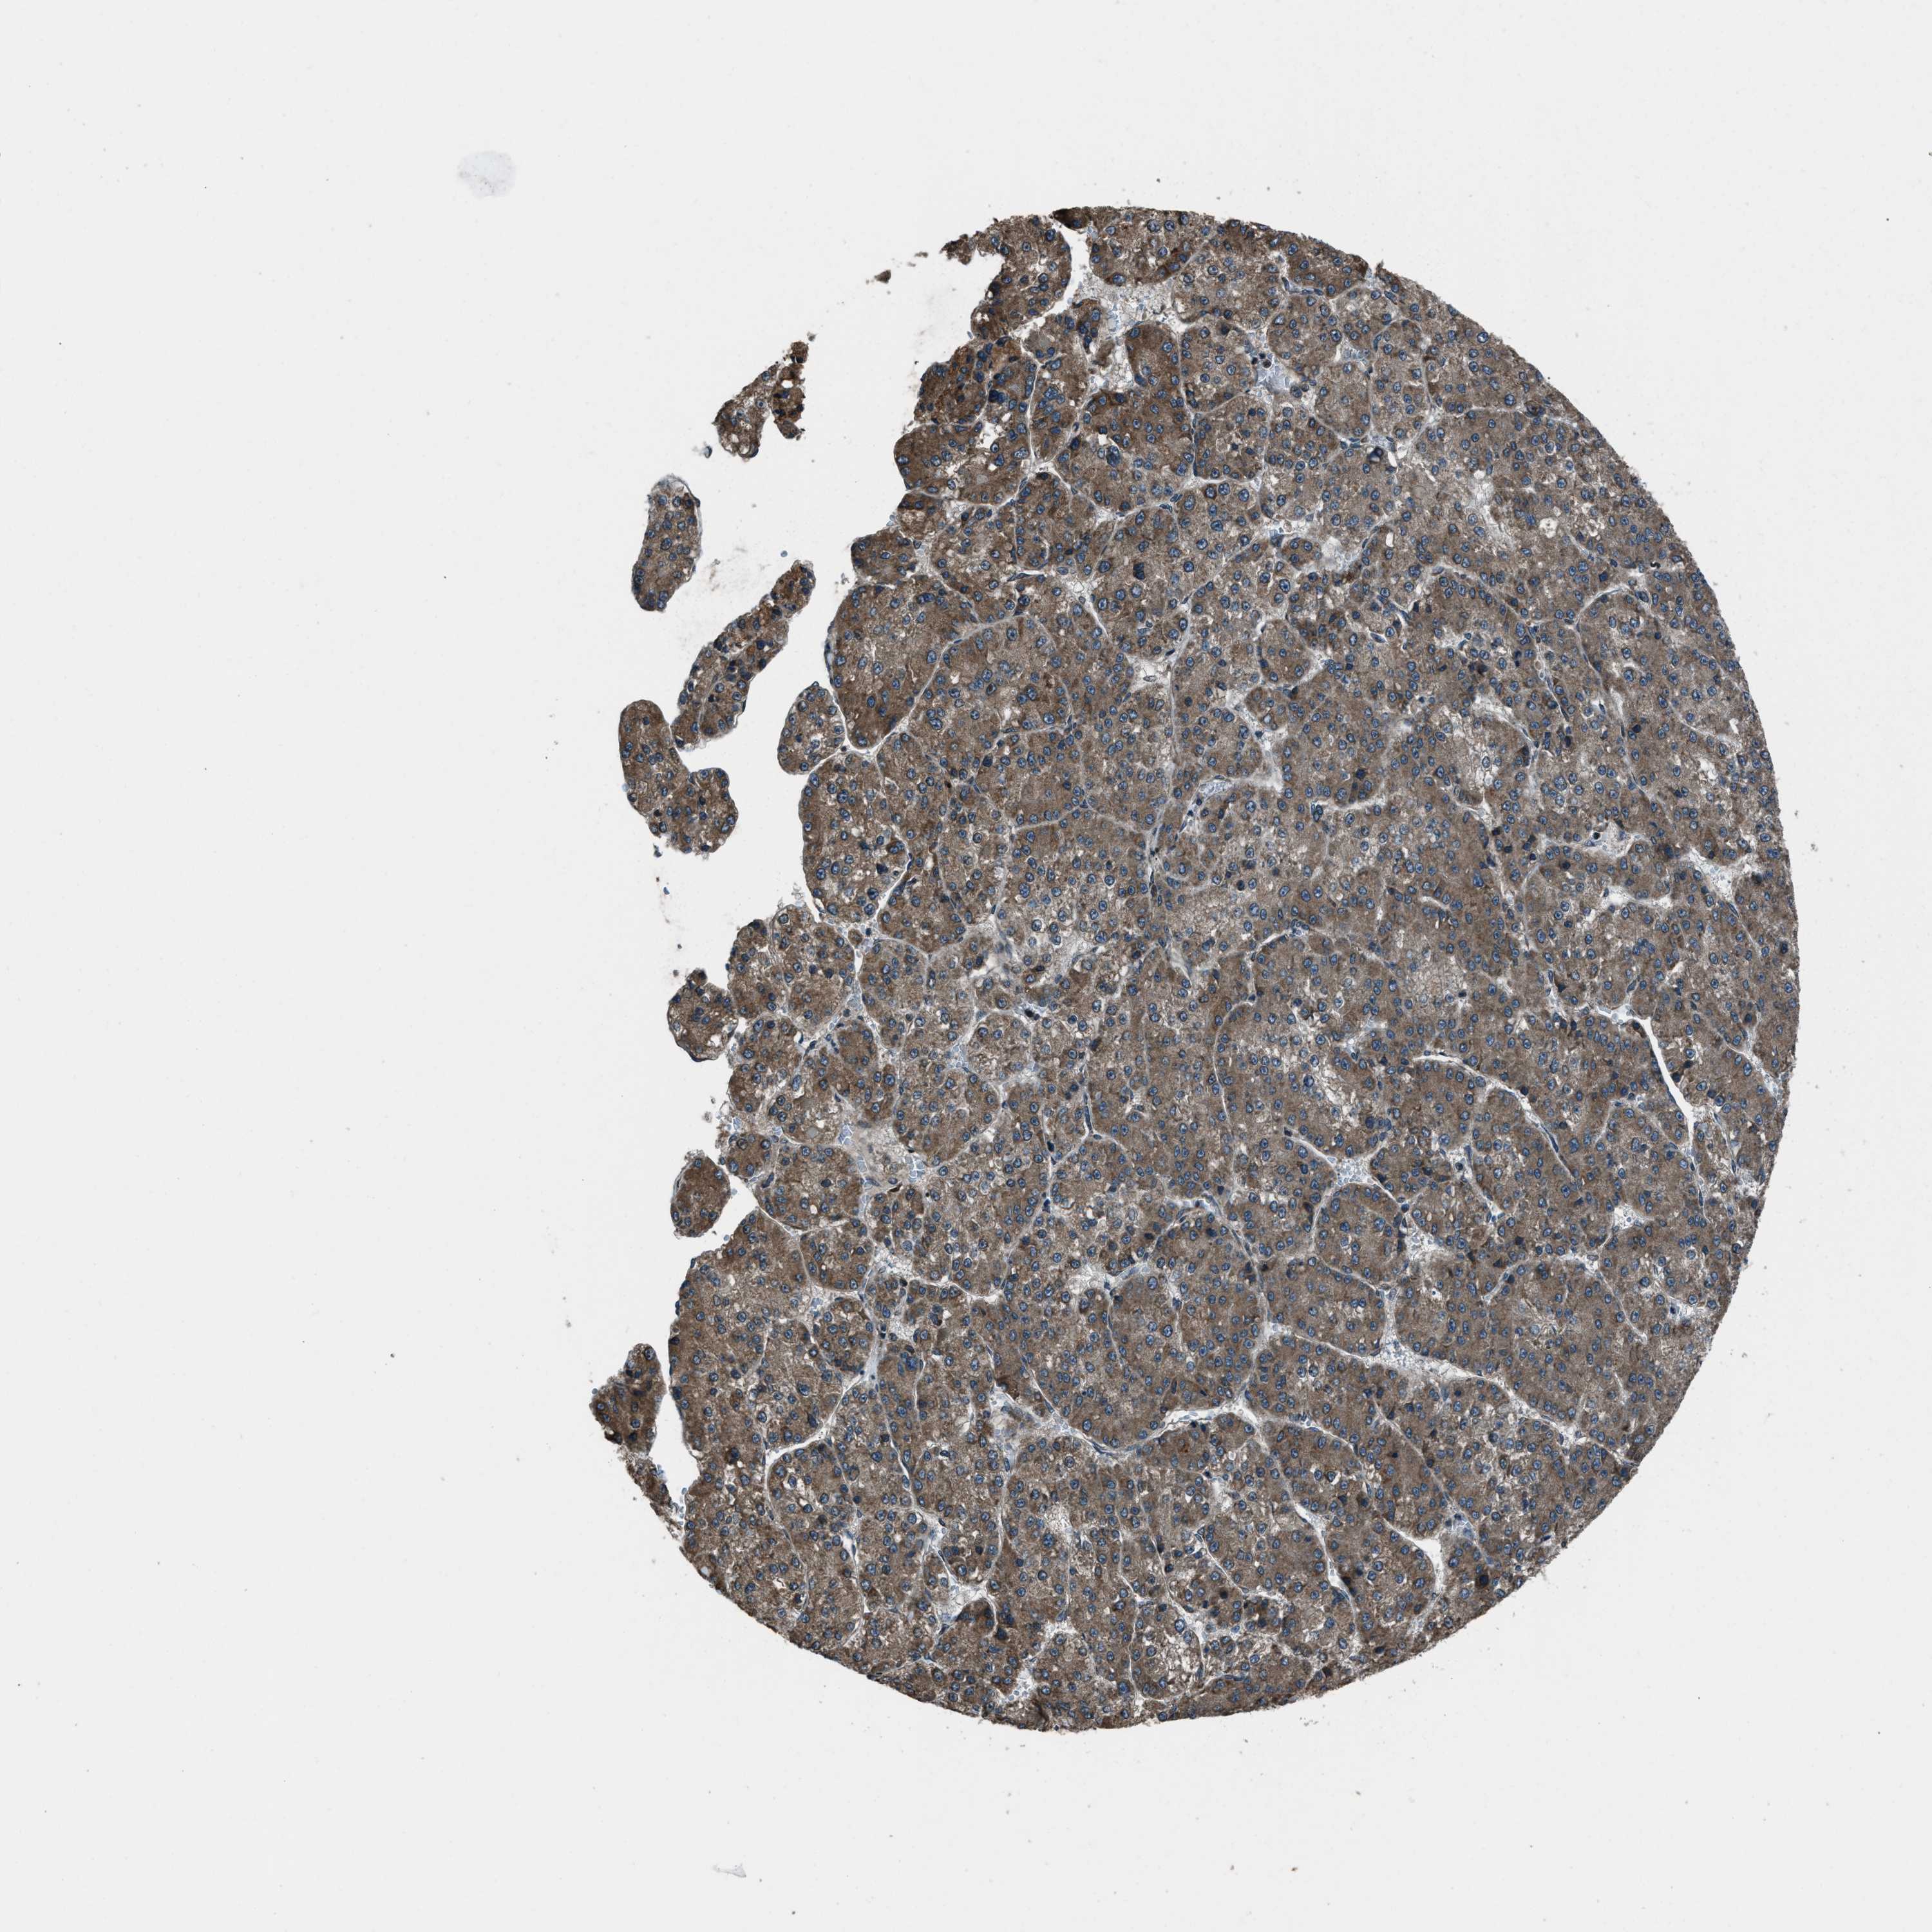

LIVER CANCER - Protein expressioni

A mouse-over function shows sample information and annotation data. Click on an image to view it in a full screen mode. Samples can be filtered based on level of antibody staining by selecting one or several of the following categories: high, medium, low and not detected. The assay and annotation is described here.

Note that samples used for immunohistochemistry by the Human Protein Atlas do not correspond to samples in the TCGA dataset.

Antibody stainingi

Antibody staining in the annotated cell types in the current human tissue is reported as not detected, low, medium, or high, based on conventional immunohistochemistry profiling in selected tissues. This score is based on the combination of the staining intensity and fraction of stained cells.

Each image is clickable and will lead to virtual microscopy that enables deeper exploration of all samples and also displays staining intensity scores, fraction scores and subcellular localization as well as patient and tissue information for each sample.

Antibody HPA019356

Antibody HPA029461

Staining

High

Medium

Low

Not detected

Intensity

Strong

Moderate

Weak

Negative

Quantity

>75%

75%-25%

<25%

None

Location

Nuclear

Cytoplasmic/membranous

Cytoplasmic/membranous,nuclear

Cholangiocarcinoma

Carcinoma, Hepatocellular, NOS